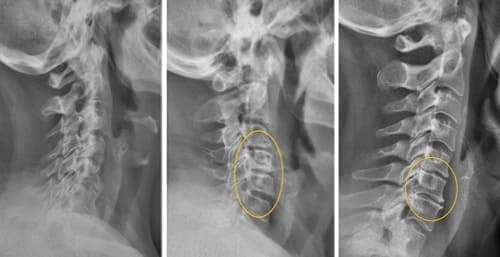

Podívejte se na tyto fotografie. To se stalo těm, kdo příznaky ignorovali. Dnes jsou bezmocní a mnoho z nich nemá na koho se o péči spolehnout. Opravdu chcete takový osud?

Všechny klouby vyžadují pozornost, ale hlavní je páteř. Postarejte se o ni, dřív než začnou nevratné změny. Podívejte se, co čeká ty, kdo ignorovali signály organismu: KÝLA, POSUN OBRATLŮ, DEFORMACE PÁTEŘE, ZHRBENÍ, ÚPLNÁ ZTRÁTA POHYBU. Nečekejte na okamžik, kdy i jednoduchý pohyb bude mučením!